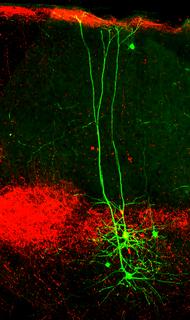

Nervenzellen Higher Order Thalamus_2

21.01.2016

Nervenzellen Higher Order Thalamus